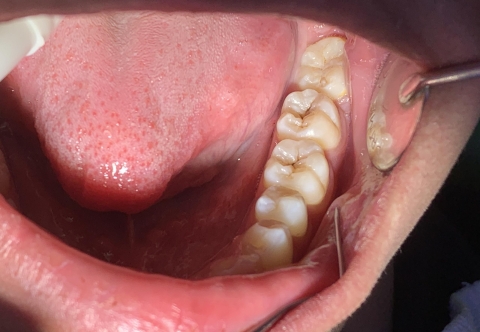

Giá chụp thép răng sữa ảnh 1

Chụp thép răng sữa sẽ:

- Giúp các con duy trì hàm răng sữa đầy đủ phòng trường hợp mất răng khó ăn uống

- Giúp đảm bảo chức năng ăn nhai, phát âm.

- Bảo vệ răng sữa, giúp hạn chế mắc phải các bệnh lý phát sinh từ vấn đề vệ sinh răng miệng.

- Tránh làm bong các miếng trám lớn, nhiều mặt, bảo vệ răng đã điều trị tủy không bị vỡ trong quá trình ăn nhai của trẻ.

- Mang đến hàm răng đều đẹp cho trẻ, giúp trẻ tự tin trong giao tiếp.